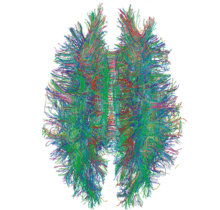

Diffusion MRI

Diffusion MRI measures the diffusion of water molecules in biological tissues.[161] Clinically, diffusion MRI is useful for the diagnoses of conditions (e.g., stroke) or neurological disorders (e.g., multiple sclerosis), and helps better understand the connectivity of white matter axons in the central nervous system.[162] In an isotropic medium (inside a glass of water for example), water molecules naturally move randomly according to turbulence and Brownian motion. In biological tissues however, where the Reynolds number is low enough for laminar flow, the diffusion may be anisotropic. For example, a molecule inside the axon of a neuron has a low probability of crossing the myelin membrane. Therefore, the molecule moves principally along the axis of the neural fiber. If it is known that molecules in a particular voxel diffuse principally in one direction, the assumption can be made that the majority of the fibers in this area are parallel to that direction.

The recent development of diffusion tensor imaging (DTI)[163] enables diffusion to be measured in multiple directions, and the fractional anisotropy in each direction to be calculated for each voxel. This enables researchers to make brain maps of fiber directions to examine the connectivity of different regions in the brain (using tractography) or to examine areas of neural degeneration and demyelination in diseases like multiple sclerosis.